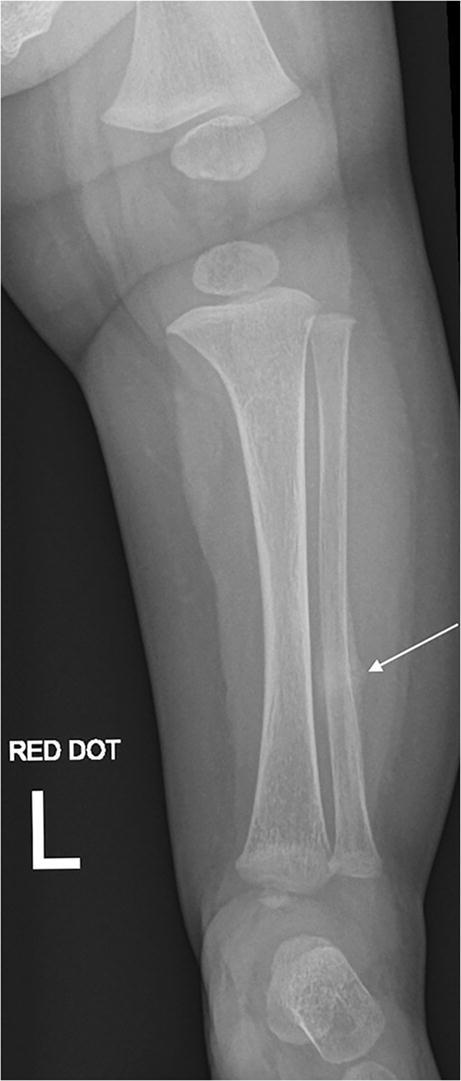

Fig. 2.

An anteroposterior radiograph of the left tibia and fibula was performed 2 days after Fig. 1, repeated due to persistent symptoms and initial “normal” radiographs. There is increased periosteal reaction (arrow) compared to the previous radiographs, consistent with progressive healing of an undisplaced fracture. There is normal density and modelling of the imaged bones